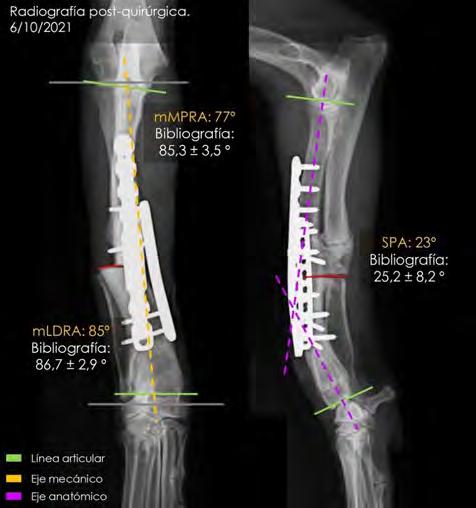

Se excluyeron del estudio los pacientes con patologías concomitantes a la ECDM, tanto cardíacas como de otros sistemas orgánicos, excepto la presencia de hipertensión pulmonar estimada mediante ecocardiografía. Se realizó la medición del volumen del atrio izquierdo con el método monoplano sumatorio de discos (MOD)9 a partir de la técnica de Simpson, que consiste en la medición del volumen del AI mediante la suma de los volúmenes de diferentes discos contiguos perpendiculares al eje mayor del AI generados por el software del ecógrafo, tras trazar el área del AI y su eje mayor de forma manual. Esta medición se realizó desde el corte paraesternal derecho longitudinal de 4 cámaras en telesístole, previo a la apertura de la válvula mitral (Fig. 1). Se siguió el borde endocárdico del atrio izquierdo, previo a la apertura de la válvula mitral en la telesístole cardíaca, sin incluir las venas pulmonares. Posteriormente, lo correlacionamos con el peso del paciente realizando la ratio: LAv/BW = volumen del atrio izquierdo (ml) / peso del paciente (kg).1,2,6

Figura 1. ECDM. (A) Medida mediante MOD del volumen del AI. (B) Corte paraesternal derecho 4 cámaras, zoom AI. Ratio LA/BW = 3, 8 ml/kg.

las guías ACVIM para la ECDM se encontrarían en un estadio C y, por tanto, en ICC izquierda, de los pacientes sin enfermedad cardíaca descompensada.